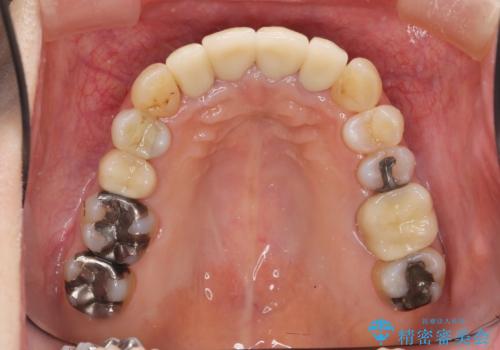

- 上顎前歯の黒ずみの改善、下顎前歯の十度なガタつき、矯正治療とセラミック治療を含む全体的な治療を希望され来院されました。

銀歯を高強度の仮歯に替えたのち、下顎前歯のみの部分矯正→全体的なマウスピース矯正治療(インビザライン)→最終的なセラミック治療と治療を進めます。

矯正治療と目立つ銀歯のやりかえを行ったことでかみあわせだけでなく、審美性・清掃性も改善し口腔内の環境を劇的に改善することができました。